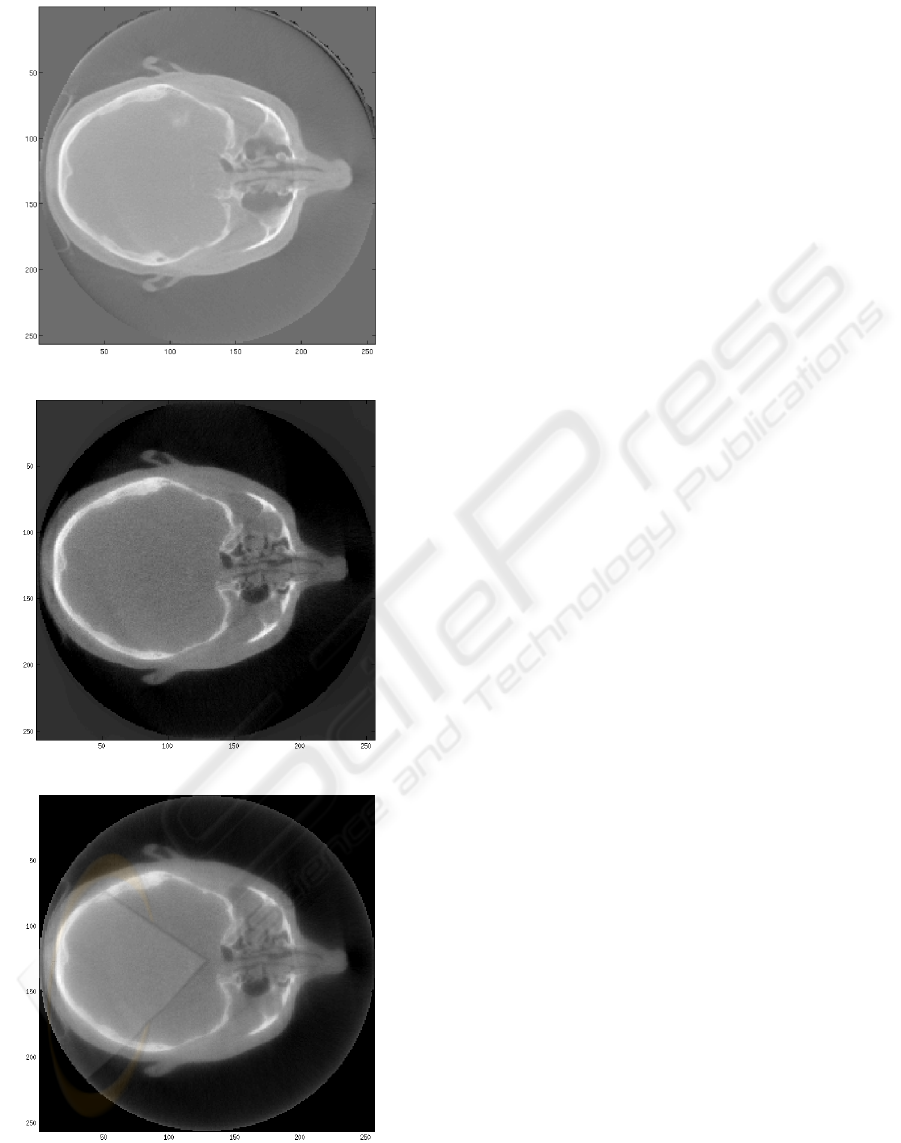

In this study, the measured projection data were

provided by North Western Medical Physics at The

Christie hospital in Manchester. A ’RANDO’ anthro-

pomorphic head phantom

1

was scanned to produce

360 X-ray projection images, approximately evenly

spaced over an angular range of -100 to +100 de-

grees. Images were acquired at 100kV, 10mA and

10ms per projection, with total imaging dose of ap-

proximately 1.5mGy. Each projection image contains

512x512 pixels of dimension 0.8x0.8mm. Figure 1

shows the imaging system used in this study.

Using the full 360 projection data set a 3D re-

construction of 256x256x256 voxels with resolution

1mm in each direction was produced using iterative